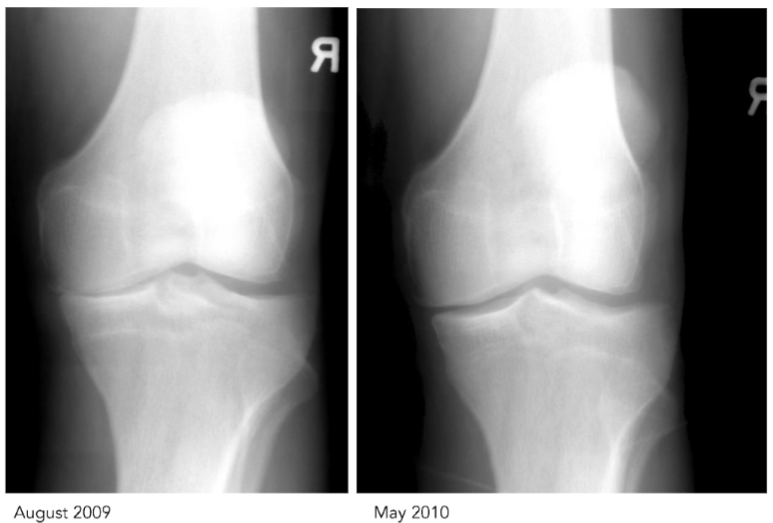

Ozone is also a non-surgical method to treat chronic pain, and has been used in various conditions including osteoarthritis, diabetes, and other inflammatory conditions. The use of ozone in dental applications has shown significant promise in treating infections and promoting healing.

- Dennis Harper, ND, DC for graciously providing pre and post OT x-rays of treated knee.